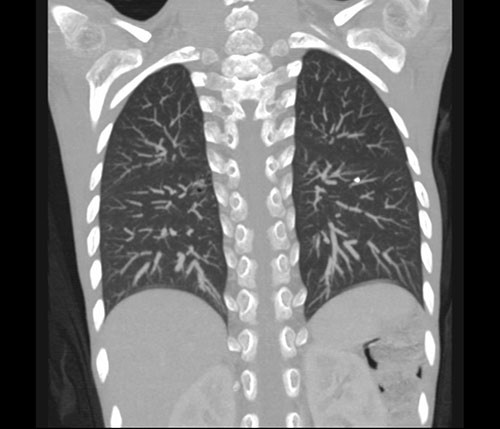

På dag 7 ble det gjort CT thorax, som viste flere forkalkede lymfekjertler i det aortopulmonale vindu og i høyre hilus (fig 1) samt en forkalkning i venstre overlapps basalfelt som kunne representere Gohns fokus, altså et tuberkuløst primærkompleks (fig 2). Man så sentrale sakkulære bronkieektasier, mest i høyre lunge, samt tynne atelektatiske fortetninger langs fissura major i venstre lunge, men ingen infiltrater eller kaverner. Oesophagus var dilatert i hele sin lengde med uttalt trang overgang til ventrikkelen.

Selv om funnene på CT thorax var mest forenlig med tidligere gjennomgått tuberkulose, kunne vi ikke utelukke aktiv sykdom. IGRA-testen var negativ, men det faktum at den viste lav mitogenkontroll, kunne peke i retning av at pasienten hadde nedsatt immunforsvar, noe som var sannsynlig på grunn av den alvorlige underernæringen.